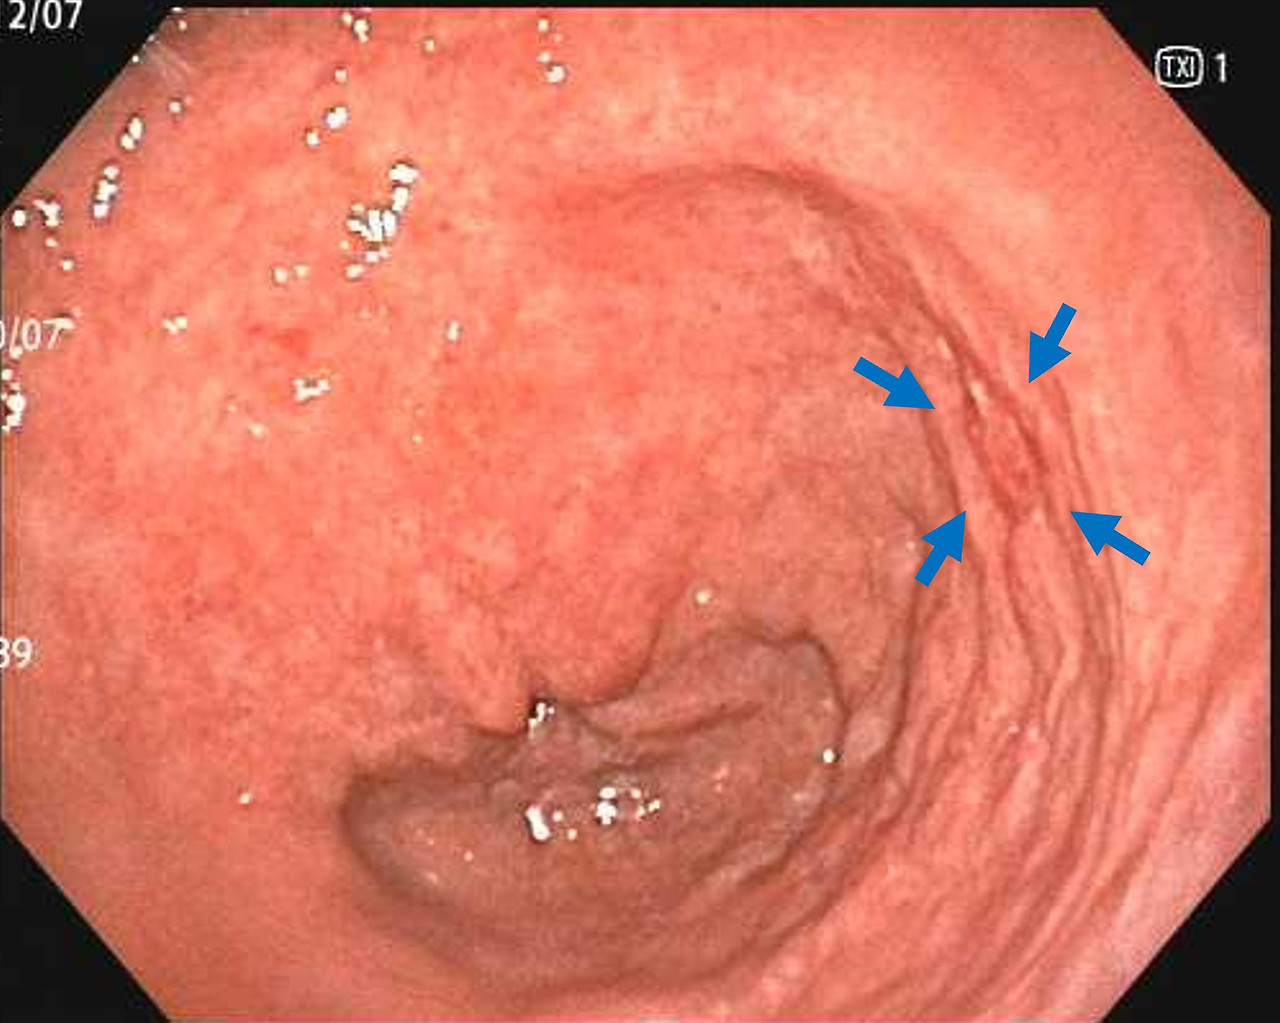

- 표면이 거칠거나 미세한 융기, 함몰이 발견되는 경우

- 미란, 궤양, 백태성 변화 등이 관찰되는 경우

- 장상피화생이 의심되는 구조 변화가 있는 경우

위내시경에서 보이는 병변은 일반적으로 ‘정상’, ‘염증’, ‘선종’, ‘암’으로 구분되지만, 실제 점막 내부의 세포 변화는 훨씬 다양하고 복잡합니다. 육안 관찰만으로 선종인지 단순 염증인지, 조기 위암인지 구분이 어려운 경우가 많기 때문에 조직검사가 정확한 확진을 내리게 됩니다.

미란·궤양의 변성 여부 평가

겉으로 보기에는 단순 궤양이지만 실제로는 악성 궤양의 형태인 경우가 있어, 의심 부위에서는 조직검사가 필수입니다. 특히 경계가 불규칙하거나 두꺼워 보이는 궤양은 초기 암일 가능성을 배제하기 위해 반드시 세포 검사가 이루어져야 합니다.

육안 소견만으로는 정상 점막과 거의 구별이 안 되는 경우가 많아,

- 색조의 미세한 차이

- 얕은 함몰

- 표면 패턴 변화

등을 근거로 조직검사를 시행합니다. 이 단계에서의 조직검사는 생명 예후와 직결되는 진단 과정입니다.